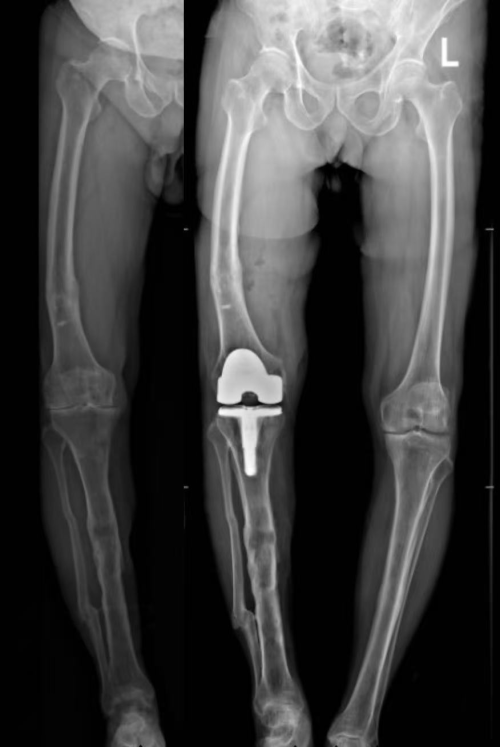

患者右膝长期呈内翻状态,行走跛行多年,同时伴有严重骨关节炎。更复杂的是,他早年曾发生右胫骨骨折,虽已愈合,但遗留骨骼畸形,导致膝关节解剖结构异常,传统手术难以精准恢复下肢力线。

图:术前术后X片对比

术后影像显示,下肢恢复至正常范围,假体安放位置与术前规划高度一致。患者疼痛明显减轻,目前已能自主站立并进行基础行走训练。